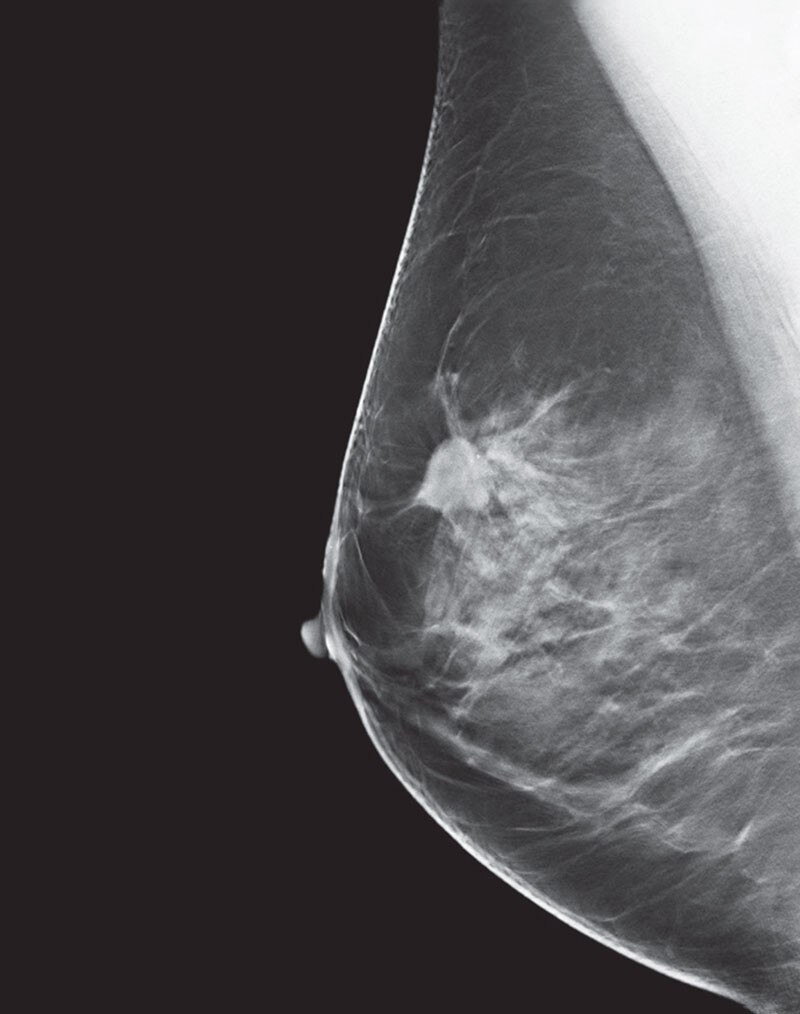

Deep learning in 3D breast image reconstruction

Pristina Recon DL

Pristina Recon DL* pushes 3D mammography past limits, delivering images with greater purity. A paradigm shift born from GE HealthCare’s pioneering AIR™ Recon DL, it operates a dual DL technology that reveals fine details, minimizing artifacts and perceived noise1,2